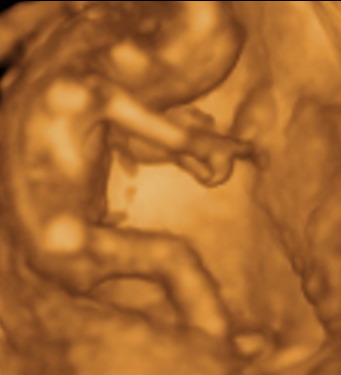

Gratula a kukishoz! Úgy tűnik minden Kisfiúnak ez a szokása! Apa akkor nagyon büszke :lol: :lol: ! Rajta múlt :D ! Kép KUKAC

Kép levitáció Kép Orr+fülfogás

Kép BOX

Kép Lúdtalp nincs :):)lábfej torna Kép Kép Álmos vagyok

Kép guggolás Kép Tipikus pasi-láb között matatás

Kép Nyújtózás

Kép Hello Kép Elég volt, most már alszom